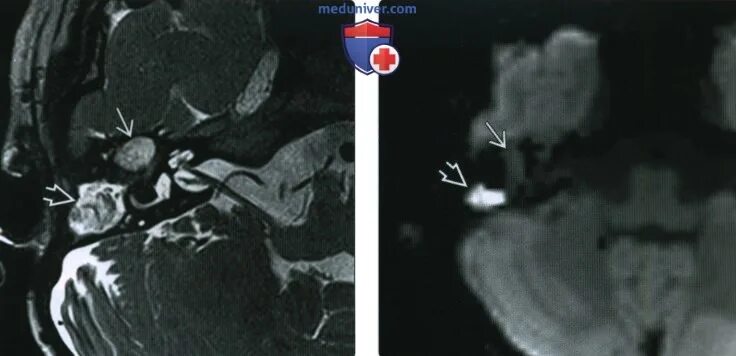

Мрт височных костей в режиме dwi